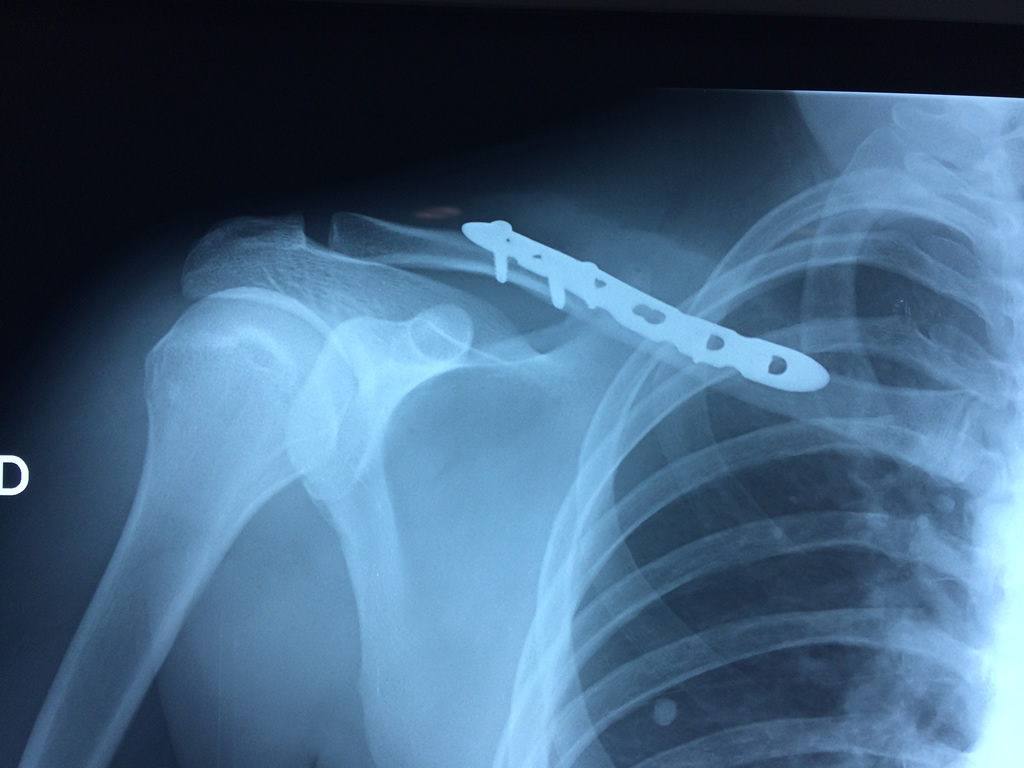

Cirugías de Húmero - Clavícula

La clavícula es un hueso largo, con forma de "S" itálica, situado en la parte anterosuperior del tórax. Junto con la escápula forman la cintura escapular. Se puede palpar por toda su longitud y se extiende del esternón al acromion de la escápula, siguiendo una dirección oblicua lateral y posterior.

Se considera el único medio de unión entre el miembro superior y el tórax. A pesar de su aspecto, similar al de un hueso largo, posee una estructura semejante a la de un hueso plano, ya que carece de epífisis y de diáfisis, lo que la harían entrar dentro de la clasificación de hueso largo. Carece de un canal medular propiamente dicho.